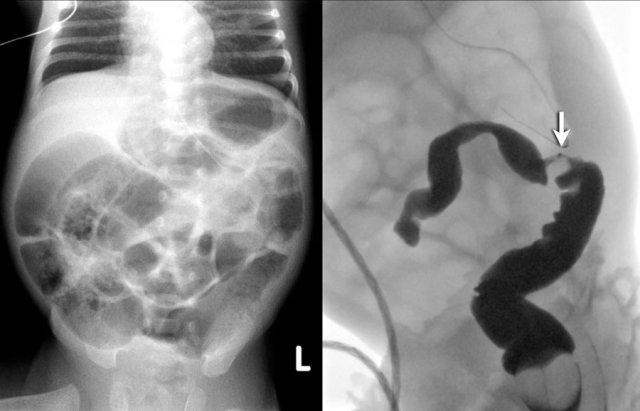

Trên hình ảnh bên trái, ruột bị giãn và đường kính vượt quá khoảng cách liên cuống L2 ở bệnh nhân tắc ruột phân su.

Trên hình ảnh bên phải, có hình ảnh giãn ruột mức độ nặng ở trẻ sơ sinh bị teo hỗng tràng.

Hình ảnh bên trái minh họa một trường hợp teo hỗng tràng.

Hình ảnh bên phải là một trường hợp teo hồi tràng.